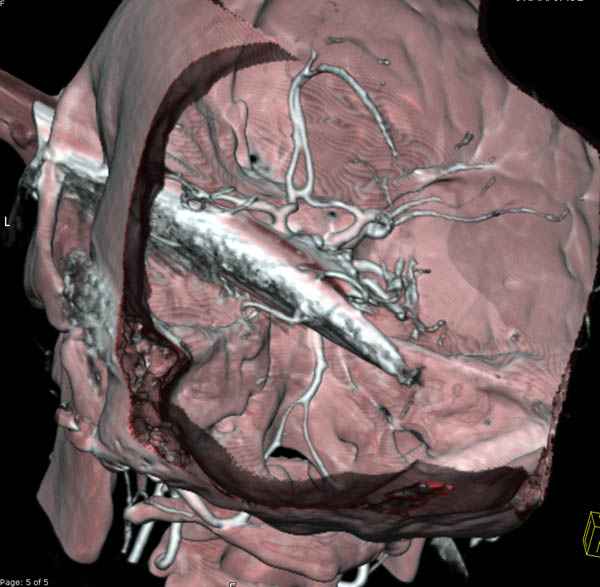

В своих выступлениях я рассказывал, что наши центры в мирное время по пенетрирующим травмам не уступает Ираку или Афганстану, и вот недавно к нам поступила больная 22 лет, травма "ножом в глаз" от бывшей подруги нынешнего "бой френда".

При поступлении в сознании, жаловалась на неприятные ощущения в глазнице.

По протоколу сделаны все необходимые исследования: рентген, ангиограмма с 3Д реконструкцией, где обнаружили что все жизненно важные сосуды не задеты, даже некоторые "сидят" изгибаясь на ноже.

Одним махом нож удалить не удалось, пришлось раскачать и потом двумя руками удалили нож. Рана без кровотечения, обработана и зашита.